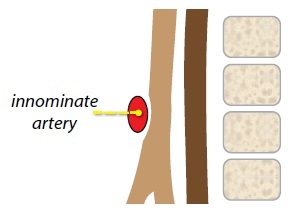

Innominate artery syndrome

In infants, the large thymus can occasionally cause the normal innominate artery to press against the anterior trachea, potentially producing innominate artery syndrome.

Innominate artery syndrome is not a vascular ring, and it is controversial whether this entitiy is a clinically relevant form of breathing difficulty.